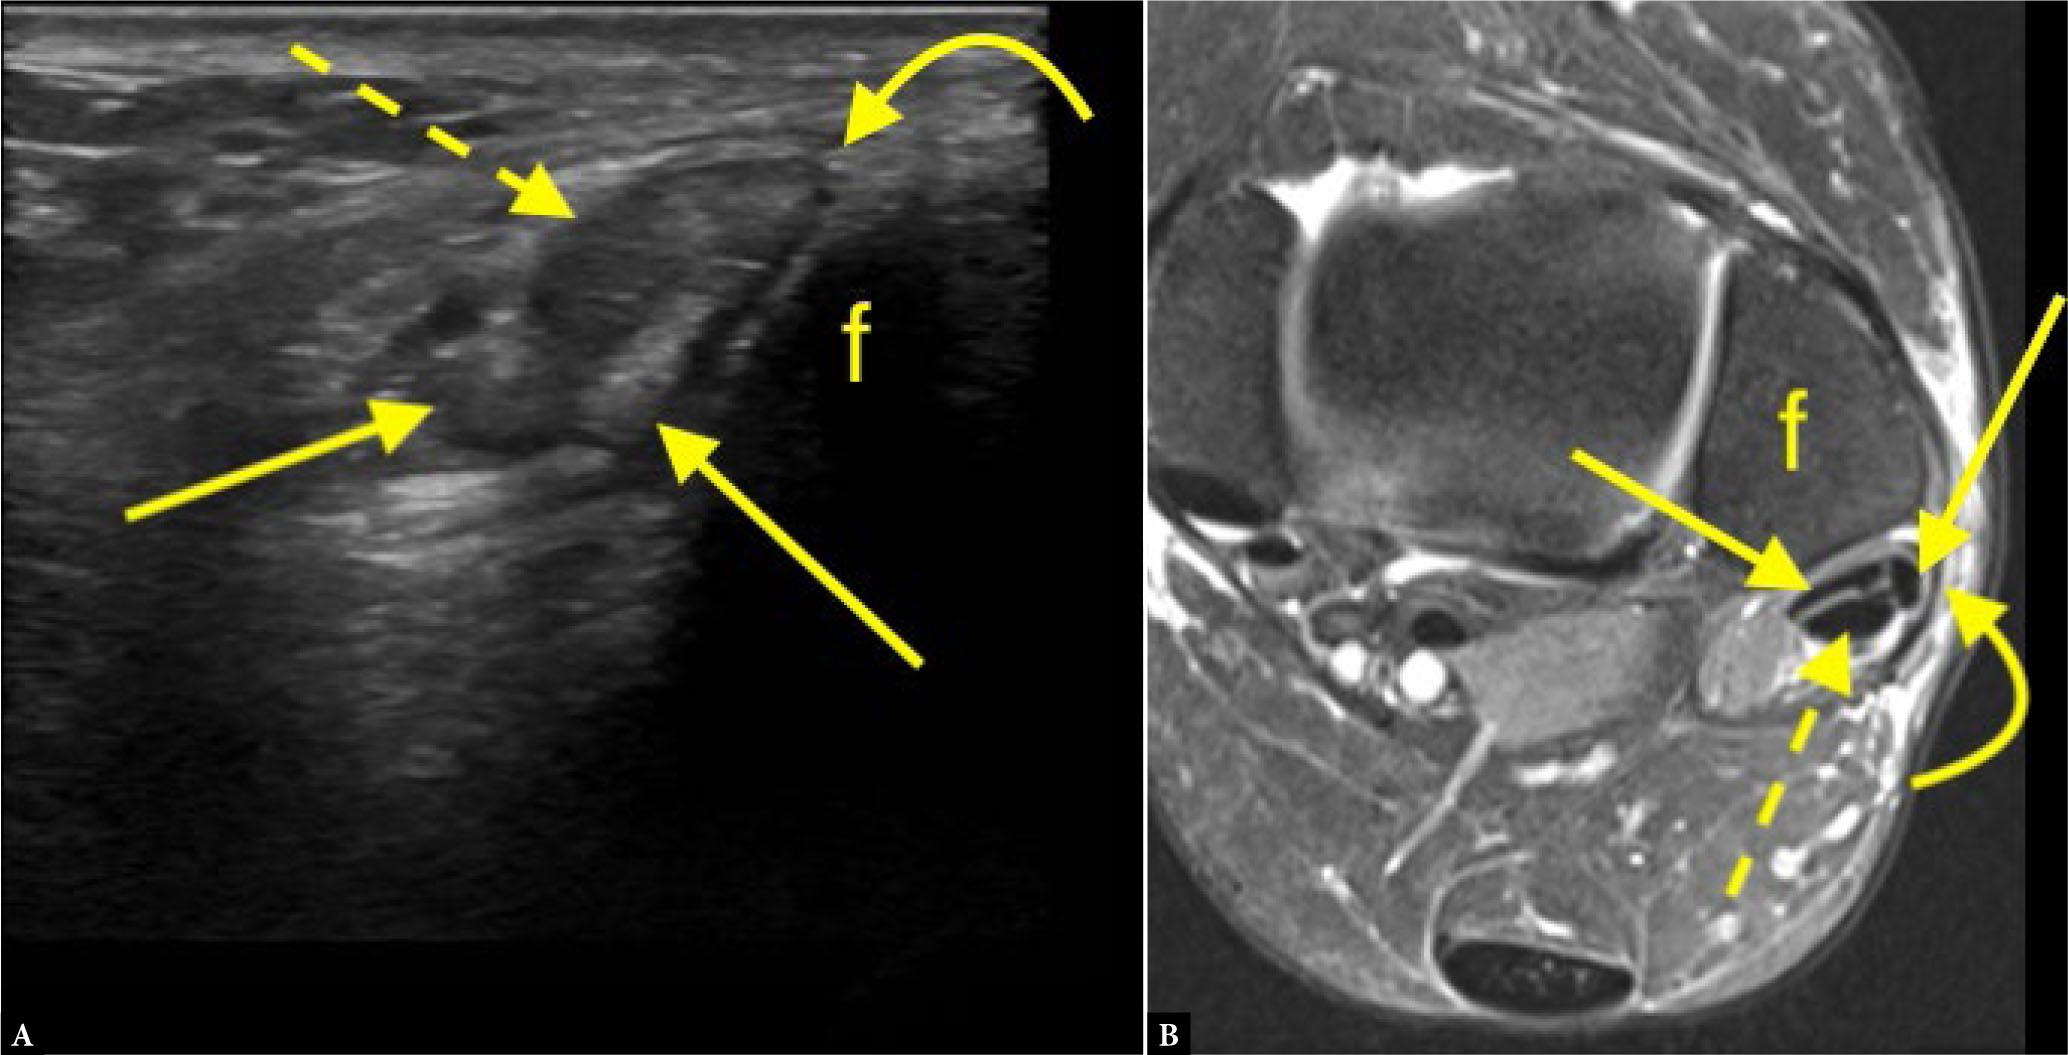

The study cohort consisted of 63 individuals, including 36 women and 27 men, aged 18 to 83 years. The mean age was 50.9 years, with a standard deviation of 16.2 years. MRI was performed in all 63 patients following their ultrasound assessment. Ultrasound examinations revealed a total of 17 split ruptures (20.7% of the patient cohort). Of these, seven cases (11.1%) were false positives (diagnosed on ultrasound but not confirmed by MRI), and nine cases (14.3%) were false negatives (missed by ultrasound but detected on MRI). Six cases (9.5%) were true positives (Fig. 1 and Fig. 2) (identified on both ultrasound and MRI), and 41 patients (65.1%) were true negatives (negative on both modalities).

True positive finding on ultrasound. A 49-year-old patient with pain posterior to the left lateral malleolus for 9 months. A. Ultrasound (transverse crosssection at the level of the lateral malleolus marked with ‘f ’) revealed a peroneus brevis split rupture. B. MRI conducted 6 months after the ultrasound confirmed the peroneus brevis split rupture (proton density-weighted image with fat suppression). Straight arrows indicate the peroneus brevis split rupture, the dashed arrow points to the normal peroneus longus, and the curved arrow indicates the superior peroneal retinaculum